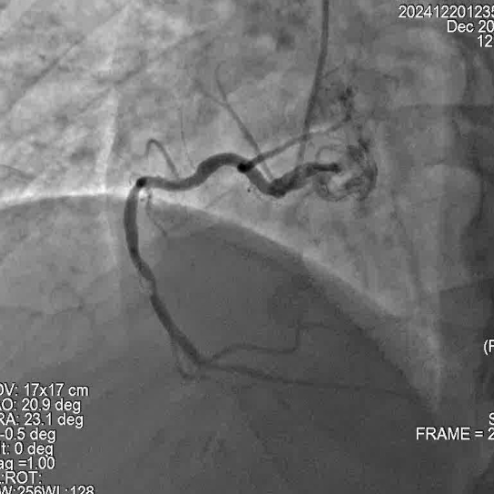

冠脉造影

手术过程

尹秋林主任表示本次手术很顺利。该患者左冠和右冠病变均较为局限,且患者及家属对植入生物可吸收支架意向强烈。在腔内影像IVUS的引导下评估管腔尺寸,病变性质后做精准预处理。本次手术中FIRESORB®具有较好的推送性,径向支撑表现也很好。我们会持续关注患者术后的恢复情况。